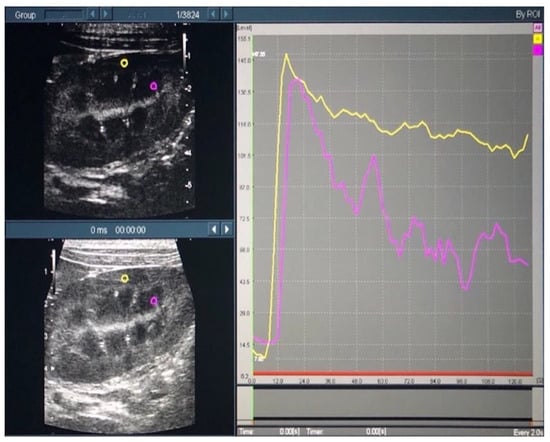

Time intensity curves (TICs) were plotted, based on the recorded contrast-enhanced ultrasound images, using the contrast harmonic imaging (CHI) analysis function of the ultrasound system. The region of interest (ROI) was set as a 2.0 × 2.0-mm circle in both the cortical and medullary regions of the left kidney (Figure 2).

Figure 2. Time intensity curves of the renal cortex and medulla in contrast-enhanced ultrasonography. In the left figure, the yellow and purple circles indicate the regions of interest in the cortical and medullary regions, respectively. In the right figure, the yellow and purple lines indicate the time intensity curves in the cortical and medullary regions, respectively.